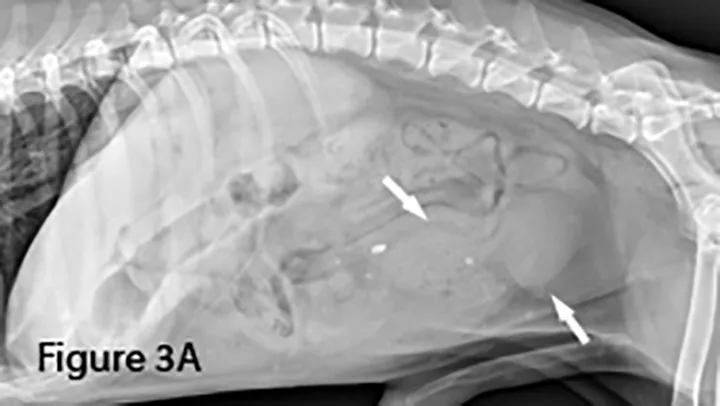

Small intestinal foreign material recognized as heterogeneous soft tissue opacity (arrows). Nearly all the small intestine is abnormally distended, indicating a distal small intestinal obstruction. The colon is empty. Distal small intestinal obstructions caused by radiographically nonopaque material warrants consideration of diffuse functional ileus. Differentiation between mechanical and functional small bowel dilation (eg, parvovirus infection, mesenteric torsion) can be difficult.